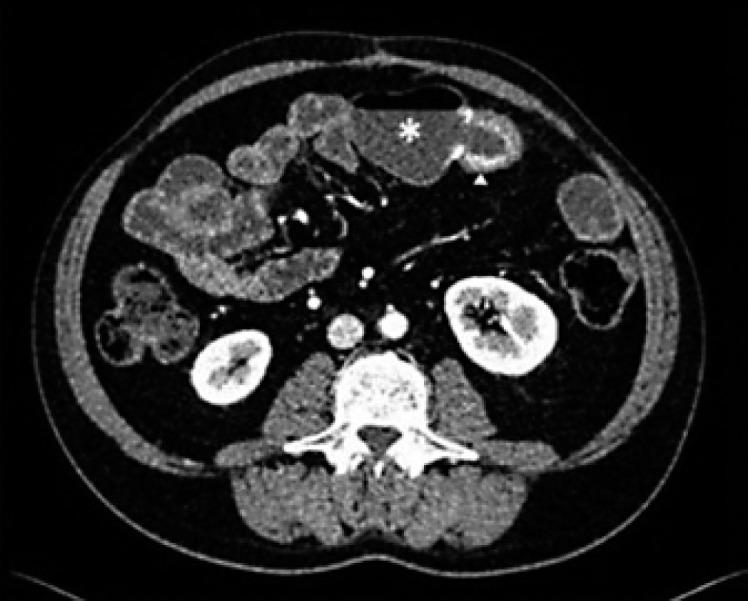

A 48-year-old male with a previous 20-year history of ileal stenosing Crohn's disease presented with iron deficiency anemia. The patient reported melena approximately 1 month earlier but was currently asymptomatic. There were no other laboratory abnormalities. Anemia was refractory to intravenous iron replacement. The patient underwent computerized tomography enterography, which revealed multiple ileal strictures with features suggesting underlying inflammation and an area of sacculation with circumferential thickening of adjacent bowel loops. Therefore, the patient underwent retrograde balloon-assisted small bowel enteroscopy, where an area of irregular mucosa and ulceration was found at the region of ileo-ileal anastomosis. Biopsies were performed and histopathological examination revealed tubular adenocarcinoma infiltrating the muscularis mucosae. The patient underwent right hemicolectomy plus segmental enterectomy of the anastomotic region where the neoplasia was located. After 2 months, he is asymptomatic and there is no evidence of recurrence.

一名48岁男性,有20年回肠狭窄性克罗恩病病史,因缺铁性贫血就诊。患者报告大约1个月前有黑便,但目前无症状。无其他实验室异常。静脉补铁治疗后贫血仍难以纠正。患者接受了计算机断层扫描小肠造影,结果显示多个回肠狭窄,特征提示潜在炎症,还有一个囊袋状区域,相邻肠袢周向增厚。因此,患者接受了逆行气囊辅助小肠镜检查,在回肠 - 回肠吻合区域发现一处不规则黏膜和溃疡区域。进行了活检,组织病理学检查显示管状腺癌浸润黏膜肌层。患者接受了右半结肠切除术加肿瘤所在吻合区域的节段性肠切除术。2个月后,他无症状,无复发迹象。